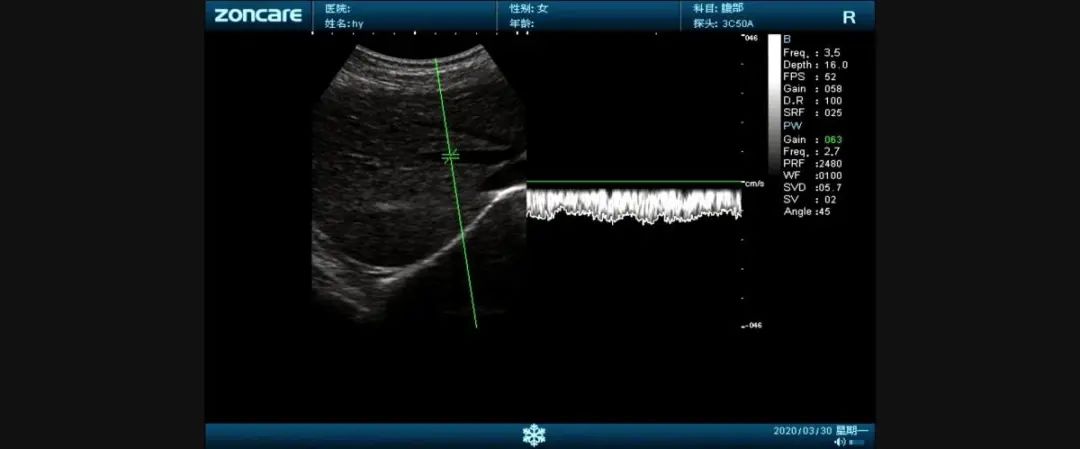

黑白B超是采用灰度调制显示声束扫描人体切面的声像图。

它们的区别是黑白超用灰度调制显示声束扫描人体切面的声像图;

彩超则是在黑白超的基础上,增加了血流信号的处理,一般用红、蓝、绿三种基本颜色,呈现出检查区域的血管分布、血流方向、血流速度等。